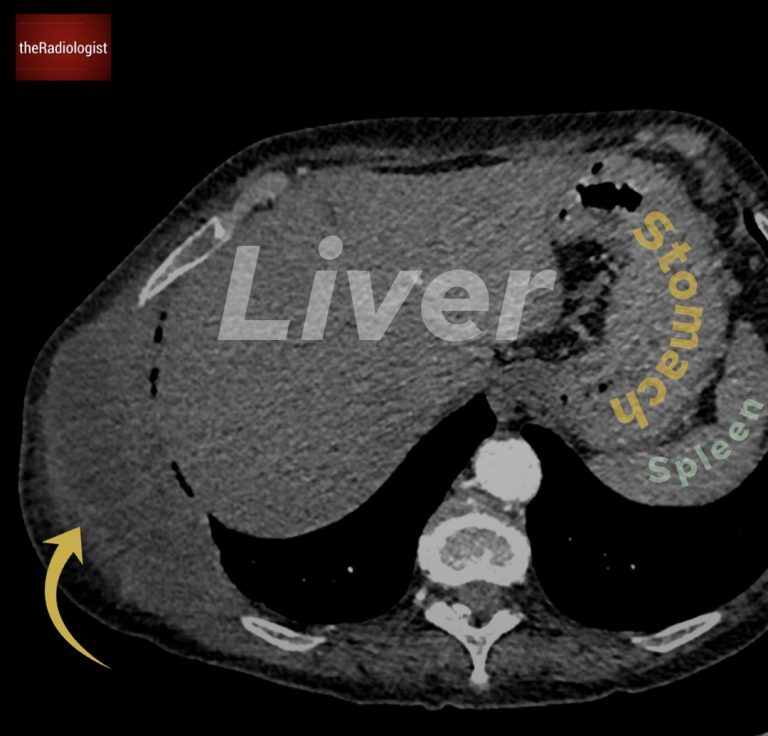

To solidify the diagnosis and to stage the patient, a CT scan was performed. As well as the cavitating lesion within the lung, it revealed a large mass invading the chest wall, clearly eroding the ninth rib. This finding strongly supported the suspicion of malignancy.

An ultrasound-guided biopsy of the chest wall mass was then carried out, confirming the presence of lung cancer with a large chest wall metastasis.

There is a soft tissue mass within the right chest wall destroying the ninth rib.